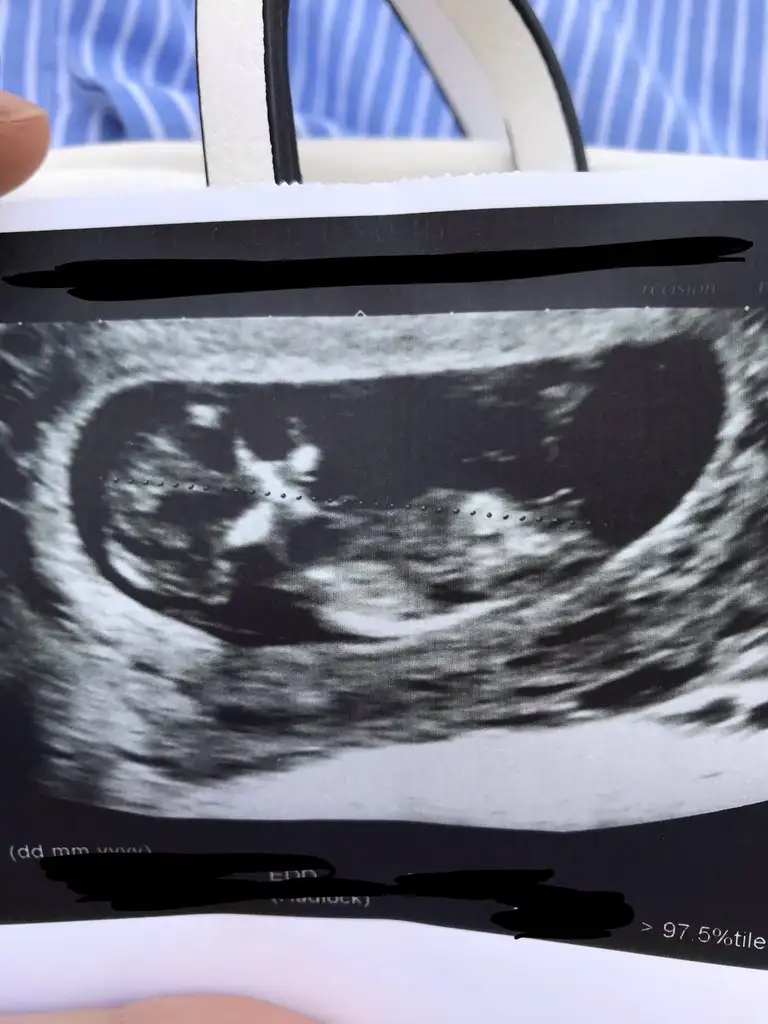

bana erkek gibi geldiCinsiyeti hakkında tahminde bulunabilir misiniz kızlar ?